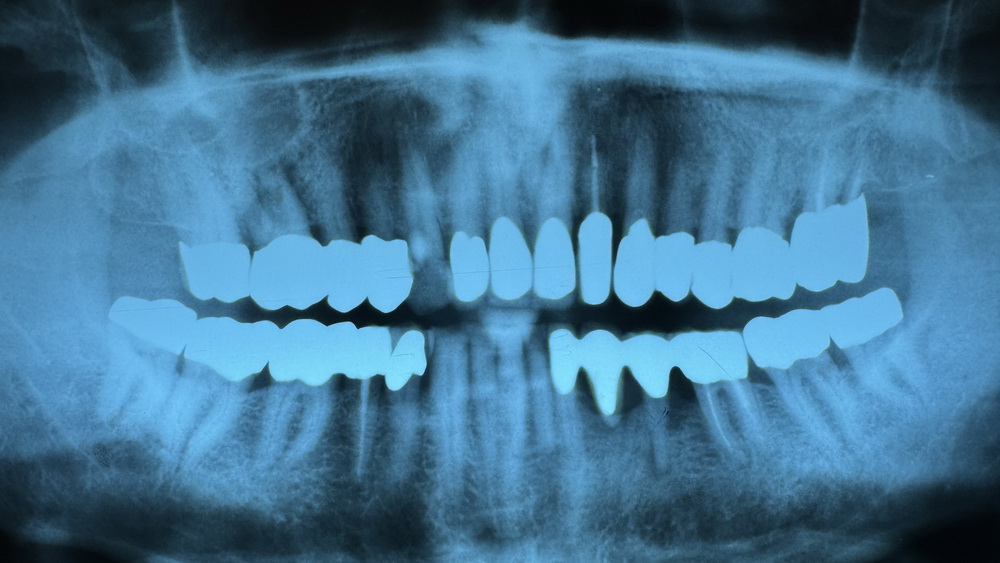

Wrum wurde das Implantat in regio 35-36 in den vorhandenen Knochen schräg eingesetzt?

Weil der Knochen in regio 35 und regio 36 aufgund der vorhandenen Knochenschädigung durch langjährige Entzündung vorgeschädigt war.

Künstlich aufgebauter Knochen ist immer gefährdeter, was eine Periimplantatitis betrifft, als vorhandener körpereigener "Altknochen".

Also, lieber ein Implantat schräg in körpereigenen Knochen gesetzt, als das Implantat auf Biegen und Brechen gerade in den Knochen zu setzen, auch wenn der Knochen dort nur eine verminderte Knochenqualität besitzt.